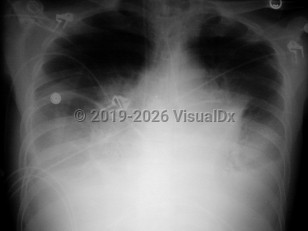

In the past, there were considered to be 2 stages of anthrax: early and late. Based on the clinical, radiologic, and microbiologic findings of the 11 inhalational anthrax victims in 2001, 3 stages have been identified.

Inclusion criteria can be any one of the following: positive blood cultures, mediastinal adenopathy, or pleural effusions. The patient may also have nonspecific findings such as high fever, dyspnea, confusion, syncope, and nausea / vomiting. If diagnosed in this stage, the prognosis is still good if antibiotics are administered, pleural fluid is drained, and supportive care is provided.